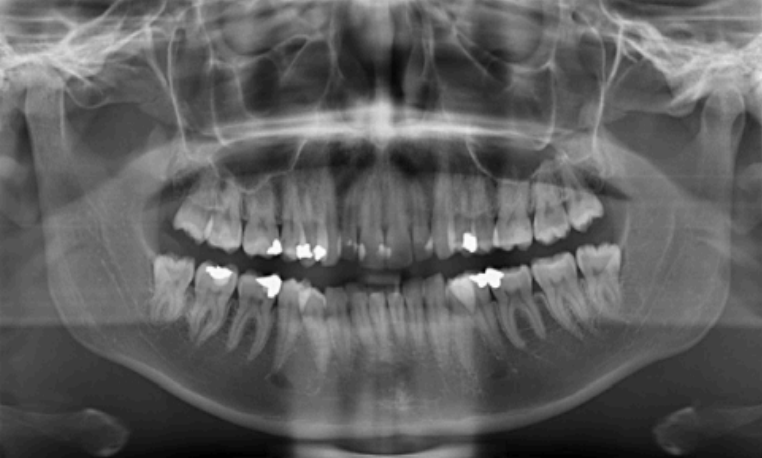

The age in this picture can be estimated by the erupted teeth which are: Maxilla ABCDE, Mandible ABCDE. The unerupted teeth are the Maxilla 1234567 and, Mandible 1234567 and the main identifying feature is the Second molar – Maxilla- 2/3 Crown completed, Mandible- 2/3 crown completed

Dental age 12 is characterized by eruption of maxillary canine and the maxillary and mandibular second premolars.

Teeth erupted– Maxilla 1234567, Mandible 1234567

Teeth unerupted – all 2nd and 3rd molars